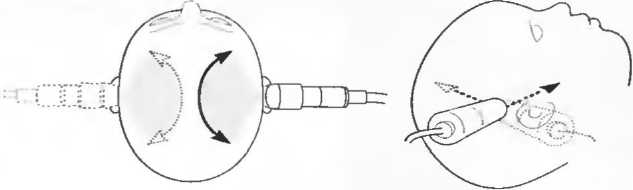

3. Ультразвуковые исследования в педиатрии. Для детей необходим датчик с частотой 5 МГц с глубиной фокусировки на 5-7 см. При исследовании мозга новорожденного используется секторный датчик с частотой 7,5 МГц с глубиной фокусировки на 4-5 см (этот датчик также используется для исследования яичек и структур шеи у взрослых).